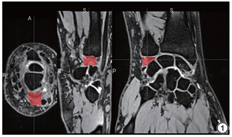

图像经吉林大学中日联谊医院放射科影像归档和通信系统(picture archiving and communication systems, PACS)获取,选取腕关节T2WI冠状位序列,经医学影像图像处理软件MRIcroGL勾画TFCC的3D感兴趣区(region of interest, ROI)。考虑到TFCC的结构及空间分布的复杂性,在勾画ROI时,以周围诸腕骨为界[22],减少TFCC本身结构性的干扰,尽管特异度可能会下降,但保证了模型敏感度。ROI由一名具有10年骨肌影像诊断经验的放射科医生勾画,并交由另一名具有15年骨肌影像诊断经验的放射科主任医师确认分割准确性,意见不一致时,讨论并达成一致意见(图1)。